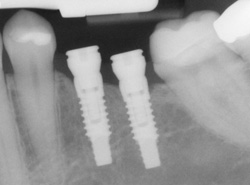

implantsIf you have missing teeth, it is crucial to replace them. Without all your teeth, chewing and eating can destabilize your bite and cause you discomfort. When teeth are missing, your mouth can shift and even cause your face to look older. Implants are a great way to replace your missing teeth, and if properly maintained, can last a lifetime!

An implant is a new tooth made of metal and porcelain that looks just like your natural tooth. It’s composed of two main parts: One part is the titanium implant body that takes the place of the missing root, and the second part is the tooth-colored crown that is cemented on top of the implant. With periodontal treatment, you can smile confidently knowing no one will ever suspect you have a replacement tooth.

implants processIn addition to tooth replacement, implants may be used to anchor dentures, especially lower dentures that tend to shift when you talk or chew. For patients with removable partial dentures, implants can replace missing teeth so you have a more natural-looking smile.